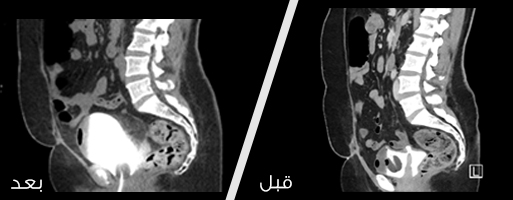

صورة اشعة قبل وبعد عملية إصلاح ناسور

نجح فريق طبي بقسم جراحة الحوض والمسالك البولية النسائية بمدينة ‏الملك عبدالعزيز الطبية بالشؤون الصحية بوزارة الحرس الوطني ‏بالرياض بإجراء عملية إصلاح ناسور بين المهبل والمثانة لسيده سعودية ‏أجريت لها عملية استئصال للرحم سابقه في أحد مناطق المملكة. ‏

ثم أجرى الفريق الطبي بقسم جراحة الحوض والمسالك البولية النسائية ‏عملية إصلاح الناسور بواسطة المنظار و ذلك تجنبا لفتح البطن .‏

وبين الدكتور الساري أن العملية تكللت بالنجاح ولله الحمد وخرجت ‏المريضة من مدينة الملك عبدالعزيز الطبية بصحه جيدة بعد يومين من ‏العملية مع وجود قسطرة بولية لمدة ثلاثة أسابيع وتم التأكد بعدها من إلتئام ‏الناسور. ‏